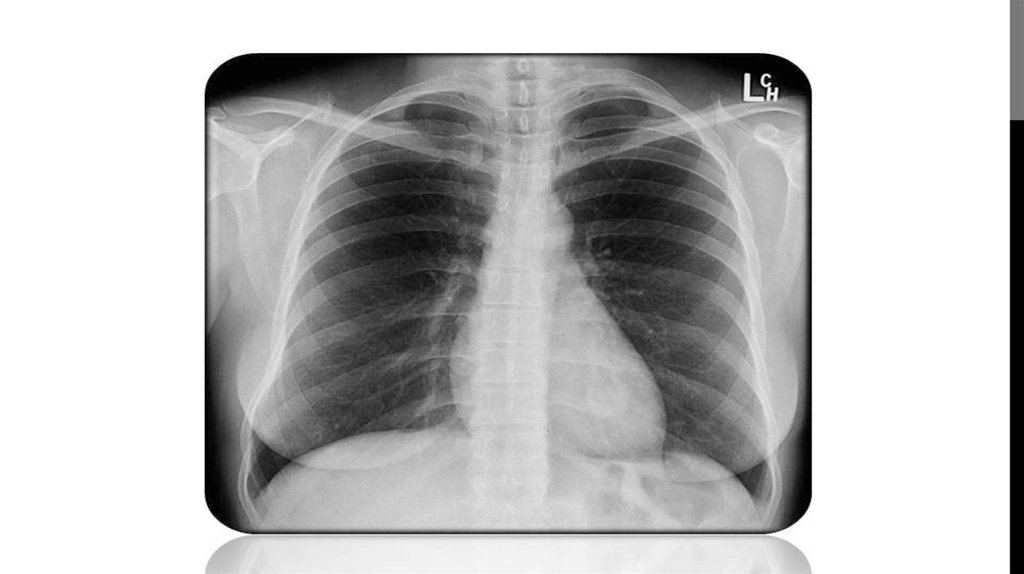

КЕУДЕ ОРГАНДАРЫНЫҢ РЕНТГЕНТ СУРЕТТЕРІ

ИНТЕРПРЕТАЦИЯЛАУ